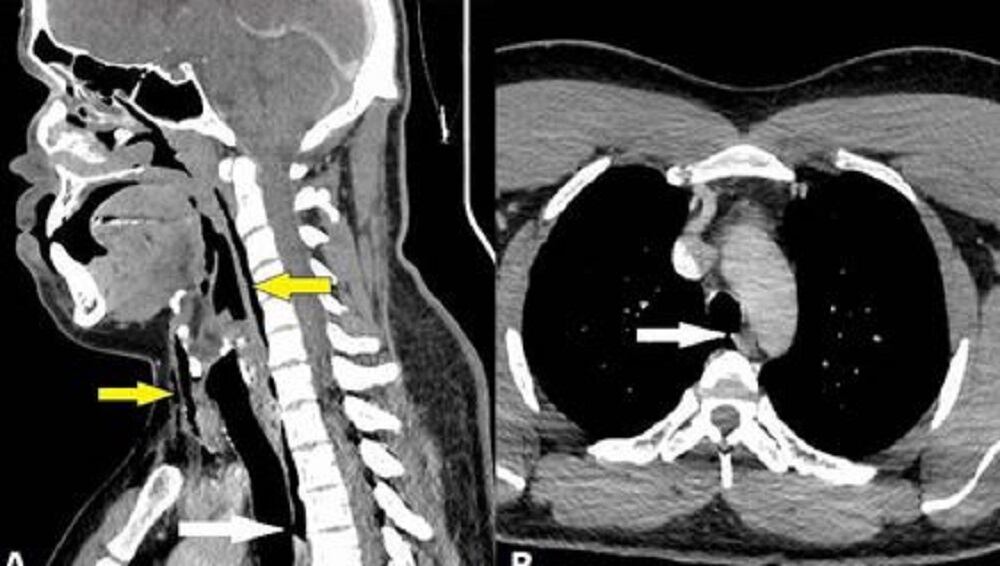

Luego, agregó: “La radiografía lateral de partes blandas del cuello reveló enfisema quirúrgico. Inmediatamente después, la TC de cuello y tórax, con contraste, reveló un desgarro traqueal entre la tercera y cuarta vértebra torácica, con neumomediastino y enfisema quirúrgico del cuello”.